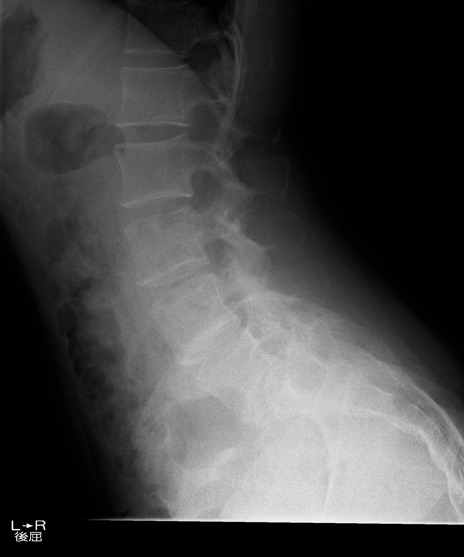

【整形】TIPS症例4 腰椎レントゲン 側面像(伸展位)

【症例】30歳代男性

【主訴】腰痛、両大腿後面の痛み

【現病歴】高校時代に●●を指摘されたが経過観察されてきた。体動時の腰痛があり、長時間立位、坐位にて両大腿後面の痛みを感じる。外来にて経過観察されてきたが改善ない。

【身体所見】SLR 60/60、TA5/5,EHL 5/5,FHL 5/5、psoas 5/5、quad 5/5、PTR+/+、ATR+/+、babinski-/-、長時間歩行で症状あるがなんとか歩いている。安静時痛なし。体動時、長時間立位、坐位にて症状あり。

異常所見と診断は?